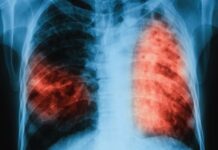

Безплатни прегледи за туберкулоза

Кампанията „Седмица на отворените врати” стартира на 18 юни и ще продължи до 22 юни. Инициативата се осъществява по Програма „Подобряване на устойчивостта на...